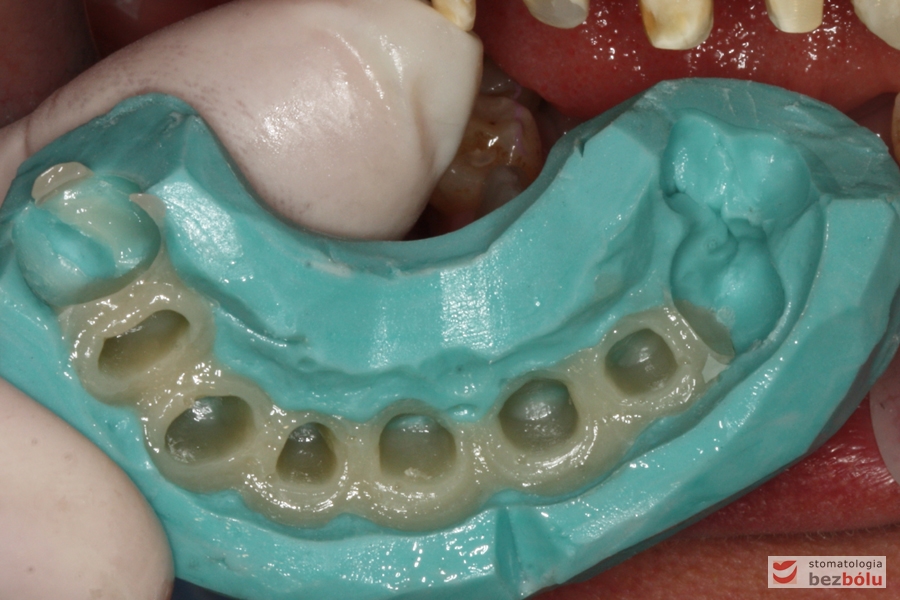

Produkcja mock-up - zastosowanie klucza silikonowego celem wykonania prowizorium

Produkcja mock-up – zastosowanie klucza silikonowego celem wykonania prowizorium